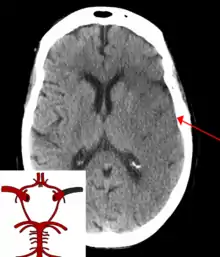

![]() | |

| CT scan of the brain showing a prior right-sided ischemic stroke from blockage of an artery. Changes on a CT may not be visible early on.[1] | |

The biggest risk factor for stroke is high blood pressure.[7] Other risk factors include high blood cholesterol, tobacco smoking, obesity, diabetes mellitus, a previous TIA, end-stage kidney disease, and atrial fibrillation.[2][7][8] Ischemic stroke is typically caused by blockage of a blood vessel, though there are also less common causes.[13][14][15] Hemorrhagic stroke is caused by either bleeding directly into the brain or into the space between the brain's membranes.[13][16] Bleeding may occur due to a ruptured brain aneurysm.[13] Diagnosis is typically based on a physical exam and supported by medical imaging such as a CT scan or MRI scan.[9] A CT scan can rule out bleeding, but may not necessarily rule out ischemia, which early on typically does not show up on a CT scan.[10] Other tests such as an electrocardiogram (ECG) and blood tests are done to determine risk factors and rule out other possible causes.[9] Low blood sugar may cause similar symptoms.[9]